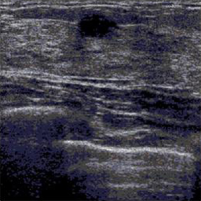

Although the proposed algorithm is independent of the imaging modality of the breast, we perform our simulations on ultrasound images, collected from the Radiology department, College of Medicine at the University of Illinois at Chicago. Our database of cancerous images show intraductal carcinoma, which is the most common type of breast cancer in women. Intraductal carcinoma is usually discovered through a mammogram or an ultrasound as microcalcifications. Our benign tumor images show the Fibroadenoma of the breast, which is a benign fibroepithelial tumor characterized by proliferation of both glandular and stromal elements.

We estimate the ARMA parameters using a window of size . The choice of the window size presents an inherent trade-off between the accuracy of the representation and the accuracy of the classification. A large window size would lead a better representation of the ARMA model, but might include pixels from different classes. We found that for images, a window size leads to a good segmentation performance. Figure 1 shows a cancerous image and a benign tumor image. Their ARMA representations are displayed in Figs. 1(b) and 1(e), respectively. It is visually clear that the ARMA model accurately represents both ultrasound images. Figures 1(c) and 1(f) show the segmentation outputs of the cancerous and benign tumor images, respectively. We can observe clear delineations of the tumors from the healthy tissues in both cases. Using the University of Illinois at Chicago’s database of ultrasound breast images, our method yields an accuracy (number of images correctly classified divided by the total number of images) of 82% (see Table 1).